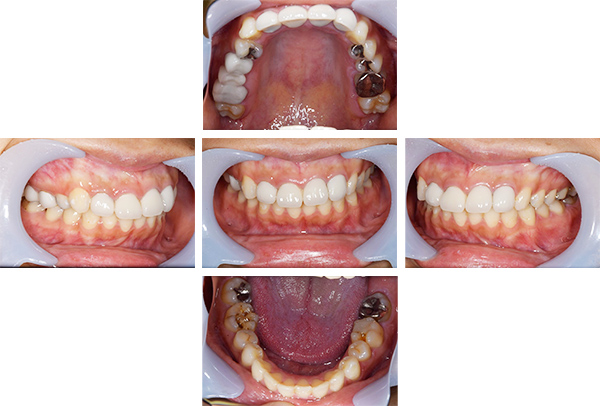

インレー症例

初診時パノラマ

初診時口腔内写真

iTero NIRI機能による診査

虫歯除去後

初診時バイトウィングデンタル

レントゲンだとちょっと虫歯が怪しいくらいに写っている。これだけだと確定診断としては、判断材料が少ないと考えられる。

黄色丸の部位が、他の部位と違って白く抜けがあるのがわかります。これがNIRI機能による虫歯の診査です。

この機能のおかげで、歯と歯の間の見つけにくい虫歯がよくわかるようになってきました。

In(インレー)セット後

当院では自費のインレー(つめ物)の場合、ゴムのシートをかけてから詰めていきます。

ゴムのシートをすることで、歯面を最大限乾燥することができ、接着力が上がる他、操作時の材料の誤飲の防止、接着剤の歯肉縁下(歯ぐきの中)への侵入を防止するなどといったメリットがあります。(歯の並びによっては、ゴムのシートができないことがあります。また、シートをかけることで苦しくなる、苦手という方には無理に行いません。)

年齢・性別 40代・男性

主訴 左上の奥歯がしみることがある

治療内容 左上4の虫歯

治療期間 2週間

リスク・副作用 虫歯の大きさによっては、神経をとらないといけなくなることがあります。

また、虫歯が大きかったケースで神経を残した場合、治療後にしみるなどの

症状が続くことがあります。

費用 ・ジルコニアインレーで修復

55,000円

治療方針

IOSのNIRI機能によって虫歯部分が明らかになったので、虫歯を除去後に修復治療を行うこととしました。

特記事項

ラバーダムは歯とつめ物をくっつける際に非常に効果的です。

人間は呼吸をしますので、お口の中はかなり湿度が高くなっています。水が多い状態でものをくっつけようと思ってもなかなかくっつかないということと同じになります。

ですので、呼気中の湿度に左右されないようにするために、ラバーダムを用いて接着力を高くしています。

ラバーダムで息が苦しくなる場合は使用しませんし、ラバーのアレルギーがある場合も使用できません。

担当医師所見

虫歯の有無を確認する上で今まではレントゲンと自分の目での確認でした。現在は目で見るよりもはるかにわかりやすいIOSという装置がありますので、虫歯の発見がしやすくなりました。

そのため、患者さんの虫歯の進行の段階が早いうちにわかる様になり、神経をとらなければならないというケースが非常に少なくなっています。